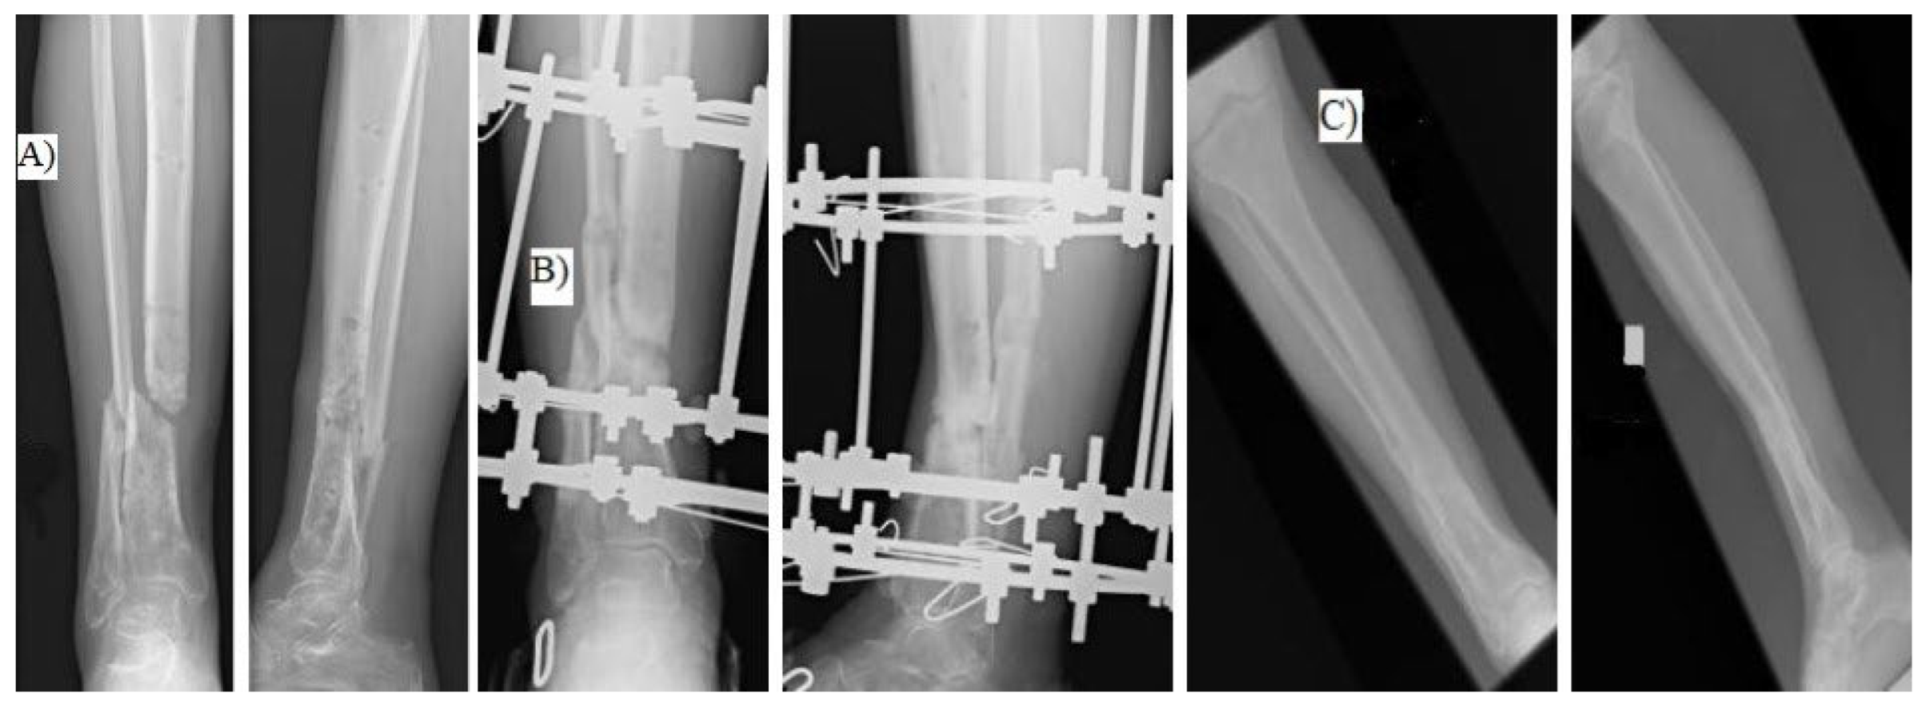

We retrospectively assessed patients with aseptic tibial shaft nonunion treated with the Ilizarov external fixator in the period 2019–2023 (Figure 1).

Figure 1. (A) patient before surgery, (B) patient during treatment with the Ilizarov method, (C) long-term result.